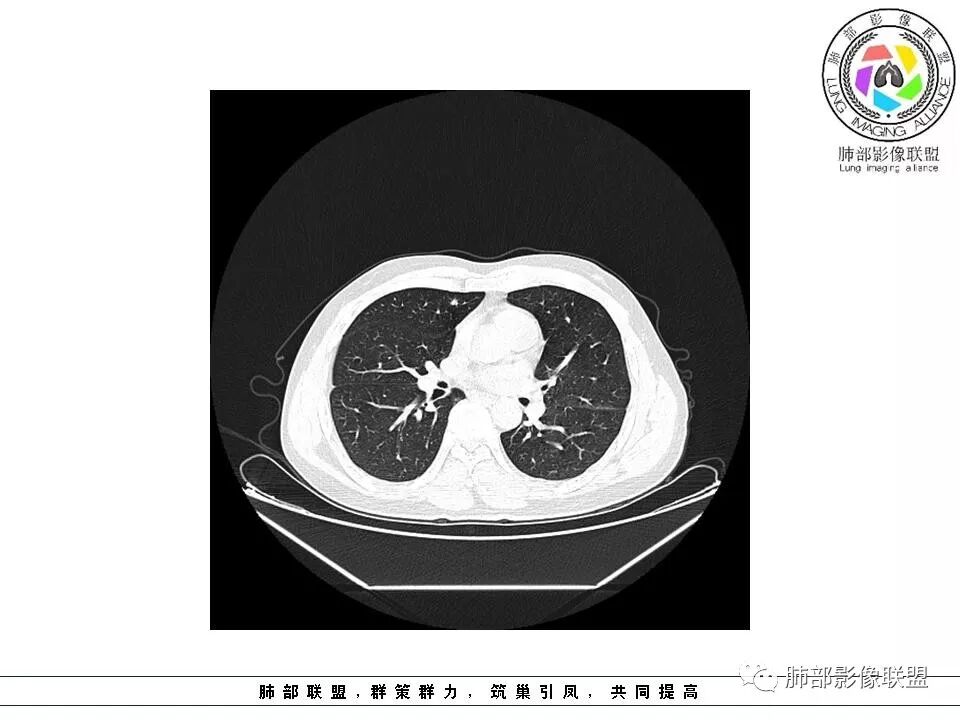

群内讨论

Ao..葉偲雨!👑:右肺中叶内侧段小结节,边缘毛刺,部分层面平直,第二次复查有凹陷,密度似乎比之前淡泊一点(肿瘤的生长周期一个月一般不会有太多变化),大小范围基本稳定,LU-Rads 4a类,炎性结节可能,建议3个月后复查或pet

南边:51岁男性,体检发现右肺结节这个年龄段的男性,啥都可以发生,也属于肺癌的高危人群南边:首先是实性还是GGO?好像实性吧

如果实性病变,边缘收缩,可以考虑炎性, 但是边缘有边界清楚GGO,一定要警惕恶性,还有粗短毛刺更要小心撇开其它,看到这个图,除非你怀疑假象,不然就是要考虑腺癌的可能

边界清楚GGO,短毛刺,这要小心瘢痕癌可以多为腺癌复查没变化,与血供有关,属于休眠期张国祯教授的理论:腺瘤样增生、原位癌都属于偏良性,就是没有侵袭性;以后发展——侵袭可以,不变可以,部分可能还会凋亡(比较少)

原位腺癌